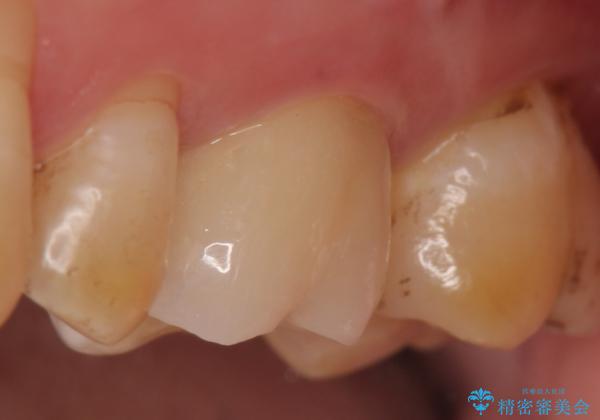

診査の結果左上6は失活していたため、根管治療を行った後にオールセラミッククラウンによる補綴を行いました。

今回用いたオールセラミッククラウンは、ジルコニアフレームという白い素材の上にセラミックを盛っているため審美性が非常に高いのが特徴です。

またジルコニアは人工ダイヤモンドの材料にも使われているほど高い強度を持っており、そのためオールセラミッククラウンは審美性だけでなく、奥歯やブリッジの補綴も可能なクラウンです。